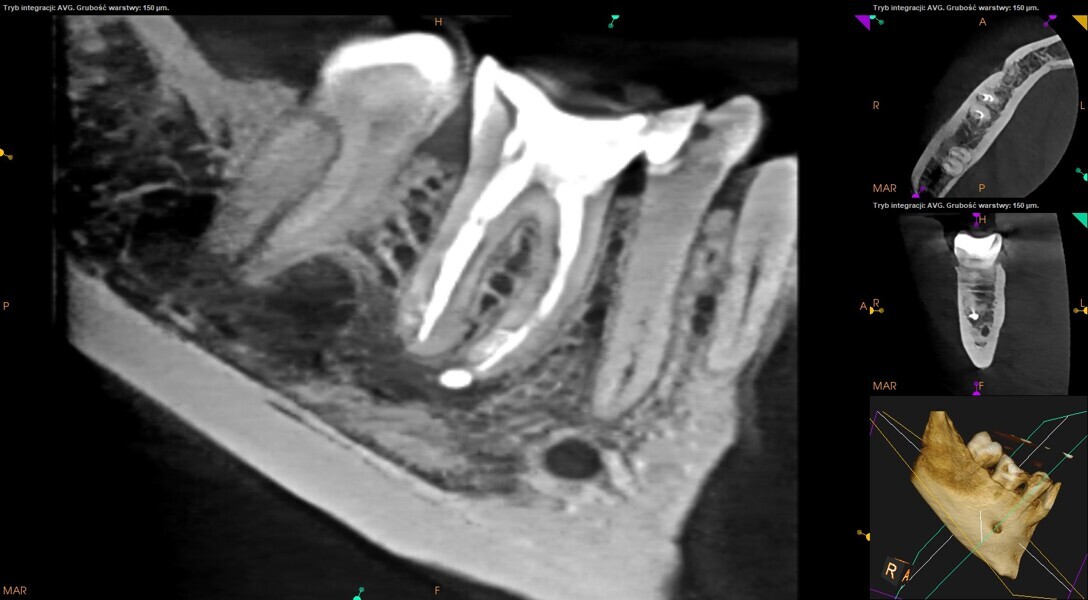

Fig. 24: CBCT scan at the six-month follow-up.

Fig. 25: CBCT scan at the 12-month follow-up.

The canals were dried with paper points and micro-suction (Fig. 21). After the irrigation protocol, there was still a lack of patency and tugback was achieved only in the mesiolingual canal. The mesiobuccal and distal canals were filled with an epoxy resin sealer and warm gutta-percha (squirting technique), and the mesiolingual canal was filled with a 30/.04 gutta-percha cone with the continuous wave of condensation technique (Fig. 22). A distally shifted periapical radiograph was performed (Fig. 23). The radiograph revealed a puff of sealer in the periapical area of the mesial root and the isthmus filled with the sealing material. A composite material was placed into the access cavity, and the patient was scheduled for the control appointment. At six months and 12 months, CBCT scans were performed (Figs. 24 & 25). The images found no signs of inflammation in the periapical area, and the tooth was asymptomatic.

After 12 months, a CBCT scan was performed (Fig. 39). The image found no signs of inflammation in the periapical area, and the tooth was asymptomatic.